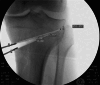

Material and methods: In this retrospective study, 40 DLOs were followed up in 34 patients. In group one (13 cases, age 45.6 (16-61) years) a varization DLO was performed, in group two (24 cases, age 48.3 (20-61) years) a valgization DLO was performed. The pre- and postoperative clinical scores were recorded: Tegner Activity score, Japanese knee society Score and Lysholm Score. The leg axis and knee joint angles were recorded and compared pre- and postoperatively.

Results: The follow-up period was 24 (6-81) months. The follow-up rate was 73% (27/37). The preoperative leg axis in group one showed an average valgus of 15.9° (9-40°). Group two had an average varus of 12° (8-21°). Postoperatively, the leg axis was 3.4° varus in group one and 0.5° valgus in group two. The mLDFA changed in group one from 83.2° to 90.9°, the MPTA from 95.5° to 87.0°. In group two, the mLDFA changed from 91.9° to 85.9° and the MPTA from 83.3° to 88.3° on average. The JLCA changed in group one from - 3.2 (- 5°-0°) to - 0.5° (- 3-2°) postoperative and in group two from 3.3° (1-8°) to 3.0° (0-6°) postoperative. Tegner score, Lysholm score and Japanese knee Society score all improved significantly in both groups. Patients with a valgus axis have worse clinical scores before surgery than the varus group, but the varus group shows a higher potential for improvement postoperatively. Every patient stated that they would have the operation performed again. Complications were rare, two overcorrections required corrective surgery. Two hinge fractures were treated intraoperatively with additional contralateral plate osteosynthesis.